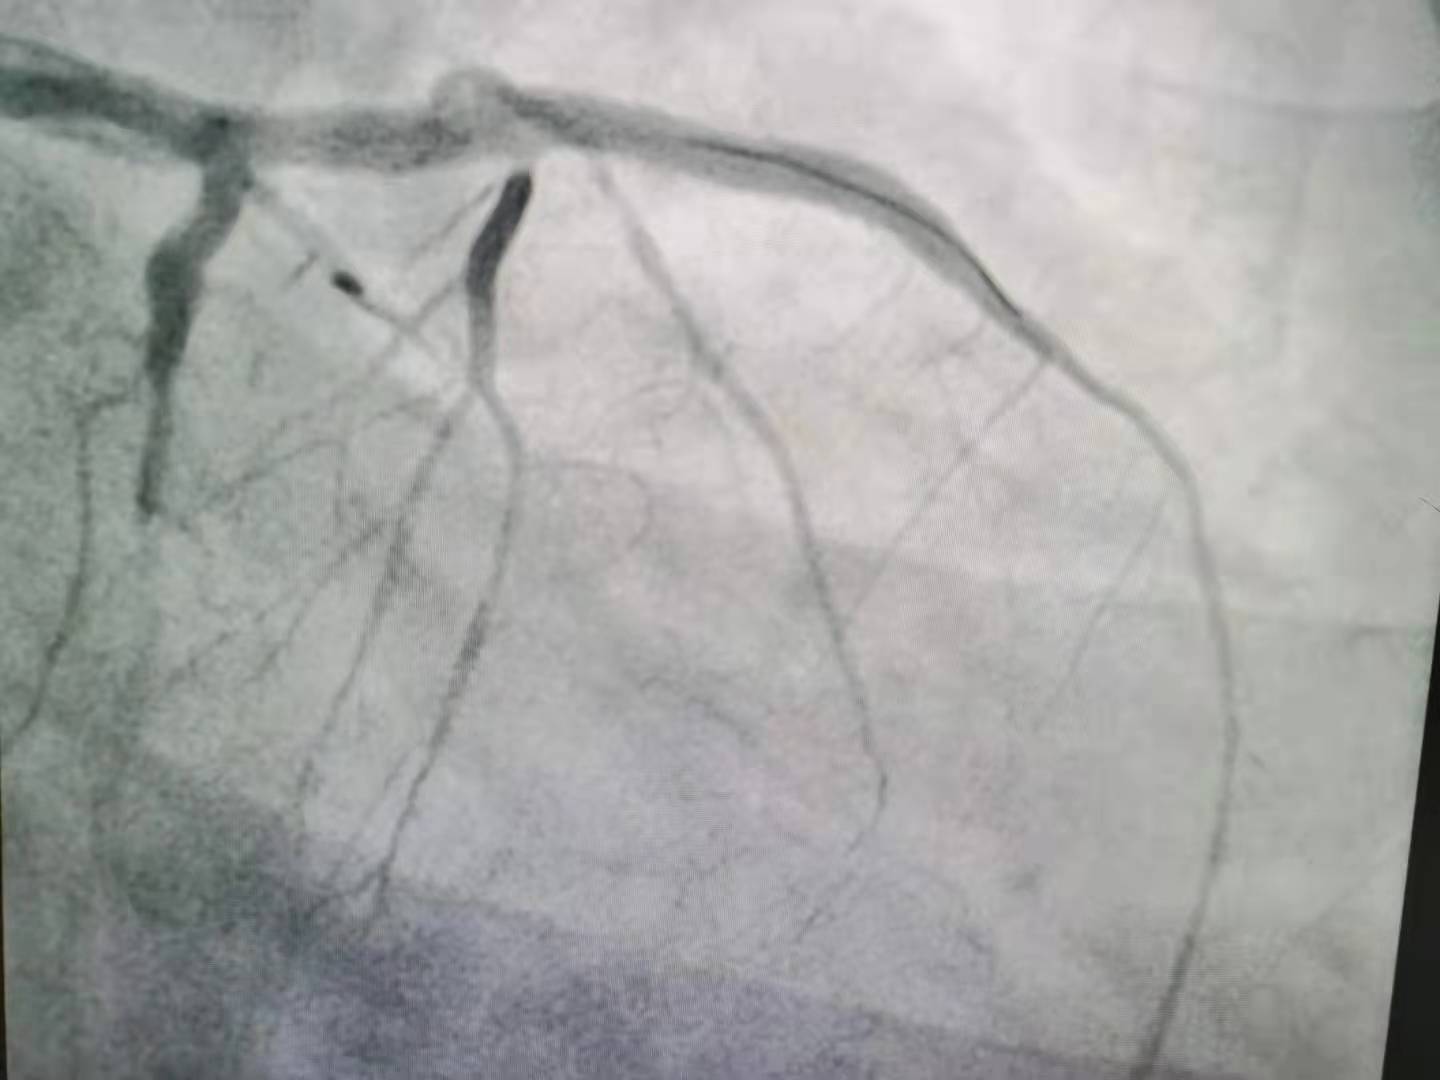

经过手术,血管成功开通。上:血管开通前,下:血管开通后。